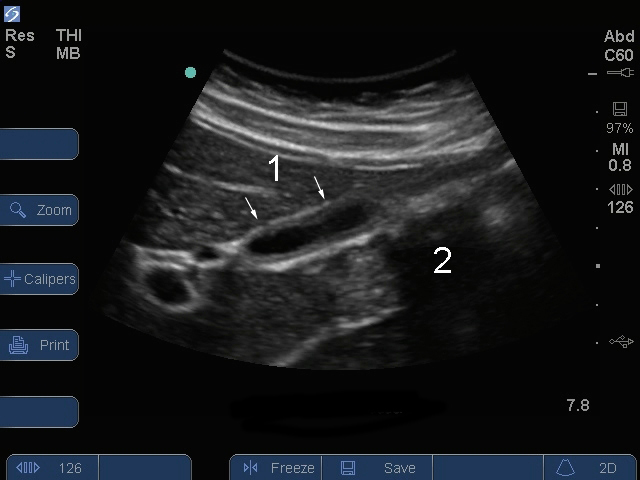

Image postprandiale - Vue longitudinale de la vésicule biliaire

1. Vésicule biliaire postprandiale

2. Gaz dans les intestins